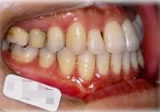

初診時年齢31歳7ヶ月。下顎側方偏位による咬合不全を主訴に来院。

顎変形と診断し、外科的処置を併用して治療。

右側面 右側面 右側面